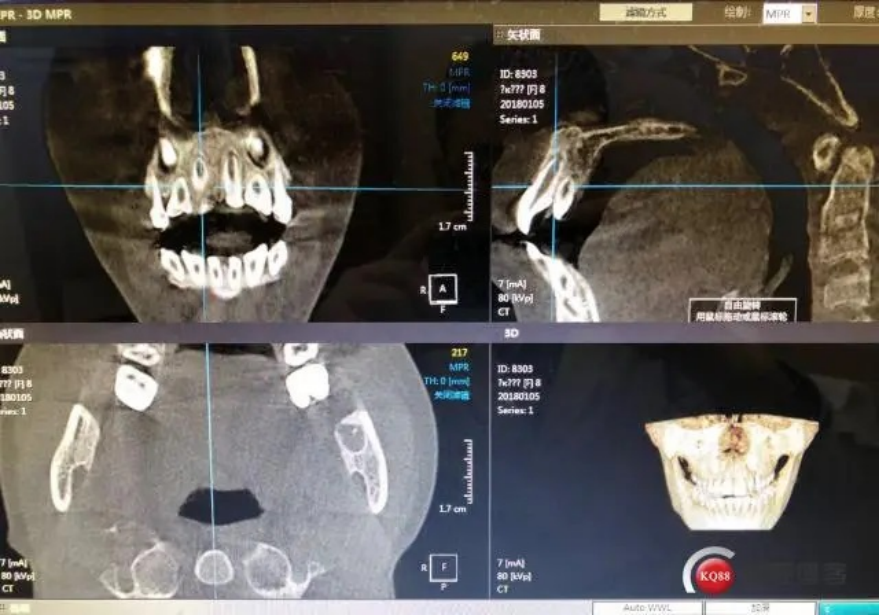

CBCT

X光拍片为什么要等小朋友看牙为什么要拍片?_https://www.jmylbn.com_新闻资讯_第10张

可以展现牙齿及颌骨三维立体结构的影像。可多角度再现颌骨、牙齿内部结构和各组织结构间的关系。